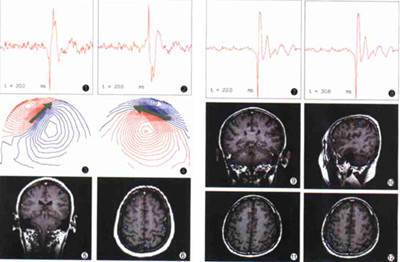

美国密苏里大学的科学家们,主要是从咒语和脑电波、脑磁场的关系角度,研究咒语的作用机理与效果。他们的研究取得了重要成果,其中最惊人的发现是“咒语会产生脑磁图”。

在默想一个咒语时,可以从不接触被试者的上,测到一个相对应的脑磁图。测了27个词语,就发出了27个词语的脑磁图。

研究人员让测试者默想一些咒语,同时用不与测试者身体接触的“超导磁强计”,来观察测试者大脑电波磁场。结果令他们十分震惊:当测试者默想咒语时,“超导磁强计”测到一个相对应的脑磁图。他们分别测试了27个不同的咒语,得到了27个不同的脑磁图。

这个实验证明,咒语的力量不只是来源于念诵时产生的声波,当我们默想时,依旧会产生磁场力量。可见意念也是物质能量的一种表现形式。